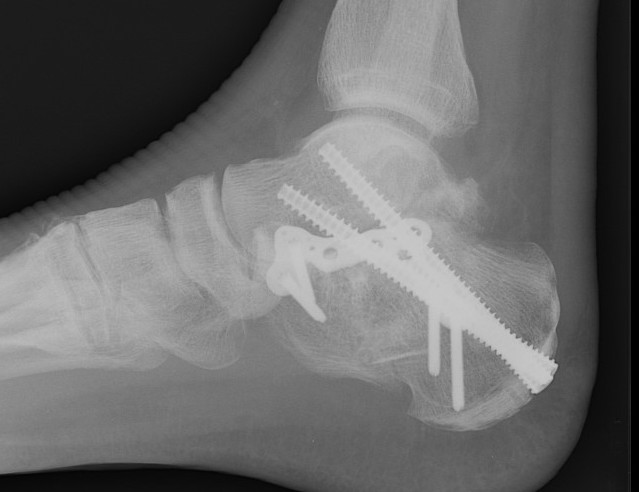

ORIF lateral plate using extensile lateral approach

Depuy Synthes calcaneal locking plates PDF

Technique

AO surgery reference extensile lateral approach

AO surgery calcaneal ORIF lateral plate

Vumedi ORIF calcaneum via extensile lateral approach

Anatomical contoured locking plate